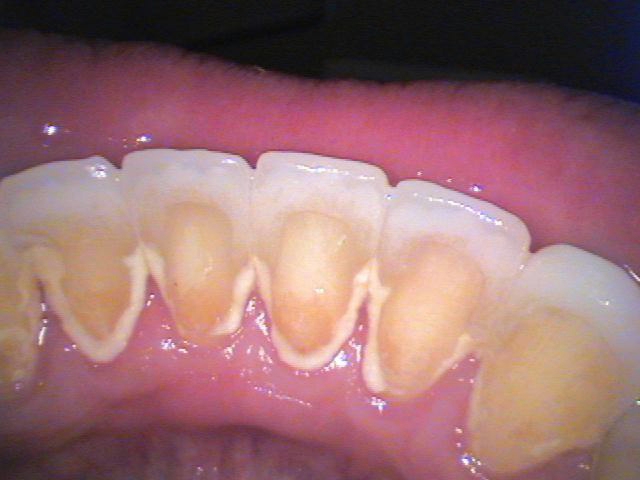

Prophy-Jet® | Our dentists are able to remove extrinsic stain, dental plaque and soft debris while simultaneously polishing the surface of your teeth!